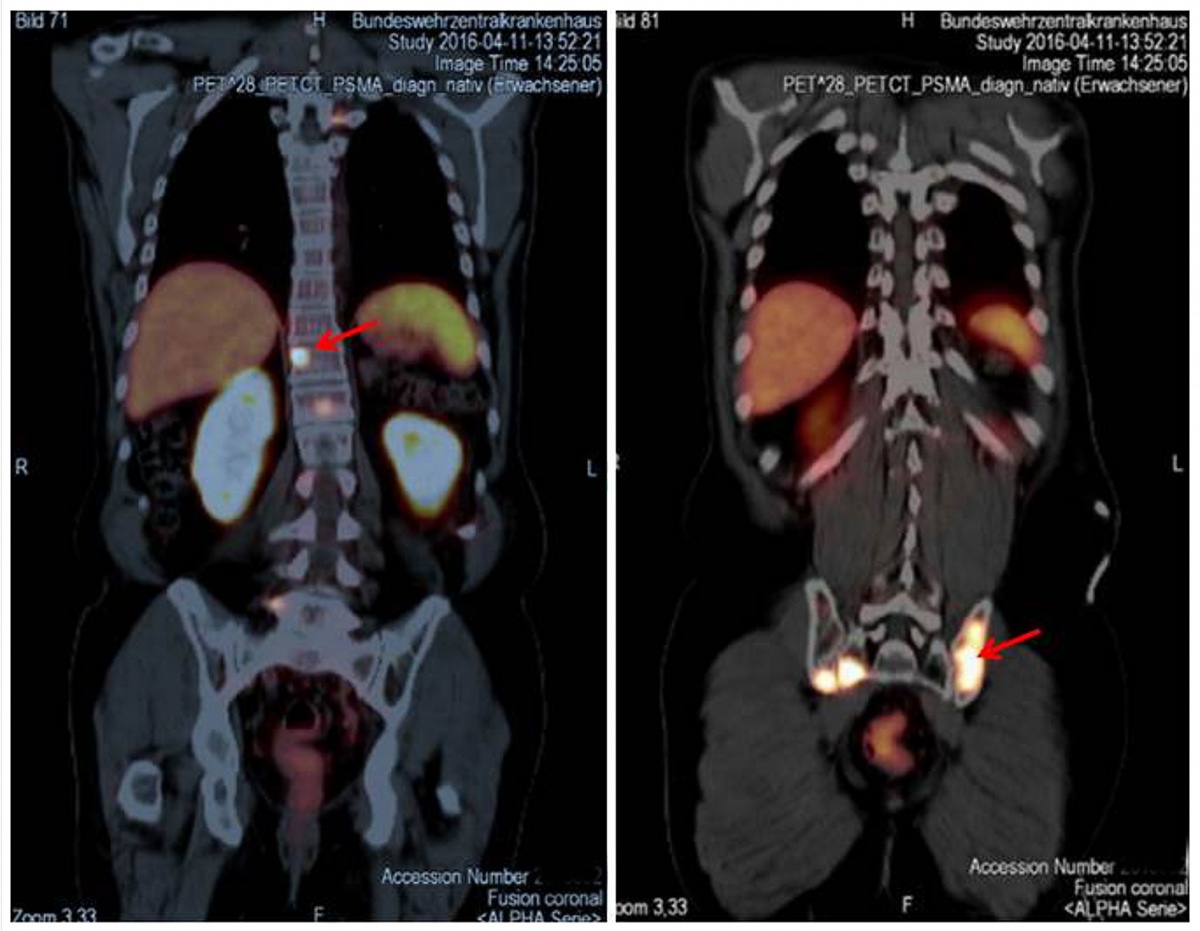

Seit Einführung der Substanz und Methode hat eine umfangreiche Zahl von Publikationen deren klinischen Wert bestätigt. So berichteten GIESEL et al. [13] in ihrer Studie, in der sie die PSMA PET/CT mit der konventionellen morphologischen Bildgebung mit CT bei Patienten vor Beginn einer Strahlentherapie untersuchten, dass mit den morphologischen Kriterien der CT, die im Wesentlichen auf Größe und Form der Lymphknoten basiert, nur 22 % der PSMA-positiven Läsionen als verdächtig für ein malignes Geschehen klassifiziert wurden. Bei zwei Drittel der Patienten erfolgte im Vergleich zwischen PSMA PET/CT und 3-D-volumetrischer CT ein „Upstaging“ von cN0 auf cN1. Vorhergehende Studien hatten gezeigt, dass diesbezüglich ein hohes Signal-zu-Hintergrund-Verhältnis typisch für die PSMA PET/CT ist [2, 4, 25]. In der gleichen Studie [13] wurde demonstriert, dass die kleinste PET-positive Läsion (in diesem Fall ein Lymphknoten) einen Kurzachsendurchmesser von nur 2,4 mm hatte. Dies bedeutet, dass man hier fast an die Grenze der physikalisch bedingten Erreichbarkeit (1,7 mm) des Verfahrens gelangt ist. Gerade beim Setting für Patienten, die für eine Salvage-Strahlentherapie vorgesehen sind, wurde der hohe Wert der PSMA PET/CT erkannt. Empfohlen wird dabei, die Salvage-Strahlentherapie am besten bei PSA-Leveln < 0,5 ng/ml durchzuführen [16, 27]. Es wurde gezeigt, dass selbst bei solch niedrigen Leveln von PSA die PSMA PET/CT in der Lage ist, pathologische Anreicherungen außerhalb der Prostata-Loge zu entdecken. Häufigste Lokalisation waren hierbei die Beckenlymphknoten in ungefähr der Hälfte der Patienten mit einem positiven PET/CT-Scan (Abbildung 2). Dies würde bedeuten, dass bei etwa einem Viertel aller Patienten, die mit solch niedrigen PSA-Leveln der PSMA PET/CT zugewiesen werden, eine Änderung im Behandlungsplan erfolgt [1, 11]. Das bedeutet, dass die PSMA PET/CT die Behandlungsabläufe beeinflussen wird, z. B. im Sinne der Vermeidung einer nicht effektiven Strahlentherapie mit nicht zu vernachlässigenden Nebenwirkungen oder etwa auch einer strahlentherapeutischen Behandlung mit Inklusion der affektierten Lymphknoten in das Strahlenfeld. Aktuelle Untersuchungen konnten auch zeigen, dass die exzellente Bildqualität, die höhere Spezifität und die gute Korrelation der PSMA-Aufnahme mit dem Gleason Score die PSMA PET der Cholin PET überlegen machen [17, 20].

infrapubisch im Nativ-CT (links) mit deutlich erhöhter PSMA-Avidität im PET (rechts)